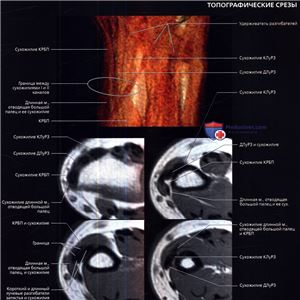

На рисунке в аксиальной проекции показаны сухожилия в проксимальном отделе запястья. Сухожилия мышц-разгибателей проходят под удерживателем разгибателей, а сухожилия сгибателей на этом уровне запястья расположены проксимальнее удерживателя сгибателей.

На соответствующем МР-срезе все сухожилия создают сигнал низкой интенсивности.

На рисунке в аксиальной проекции показаны сухожилия в запястном канале. Сухожилия глубокого сгибателя пальцев направляются к мизинцу, безымянному, среднему и указательному пальцам параллельно друг другу (от медиальной стороны к латеральной). Из сухожилий поверхностного сгибателя пальцев два глубоких сухожилия направляются к среднему и безымянному пальцам и два поверхностных сухожилия проходят к мизинцу и указательному пальцам. Сухожилие длинного разгибателя большого пальца проходит над сухожилием короткого лучевого разгибателя запястья (КЛуРЗ).

На соответствующей рисунку аксиальной МРТ показаны сухожилия в запястном канале. Обратите внимание на феномен «магического угла» на ДРБП в месте его прохождения над КЛуРЗ. Сухожилие находится под углом 55° к главному магнитному полю, что приводит к потере нормального низкоинтенсивного сигнала.

На первой из шести отобранных аксиальных МР-томограмм показан ход сухожилий и их отношение к окружающим костным структурам. Удобным костным ориентиром служит бугорок Листера, разделяющий II и III каналы разгибателей.

Удерживатель разгибателей удерживает сухожилия разгибателей в шести отдельных каналах.

Срединный нерв имеет округлую форму и лежит кнаружи и латеральнее сухожилий сгибателей пальцев.

Обратите внимание на феномен «магического угла» на ДРБП в месте ее пересечения с КЛуРЗ.

Удерживатель сгибателей огибает запястный канал от бугорка ладьевидной кости до крючка крючковидной кости. Его поверхностные волокна образуют крышу канала Гийона.

Удерживатель сгибателей прикрепляется к гребню кости-трапеции с латеральной стороны и крючку крючковидной кости — с медиальной.